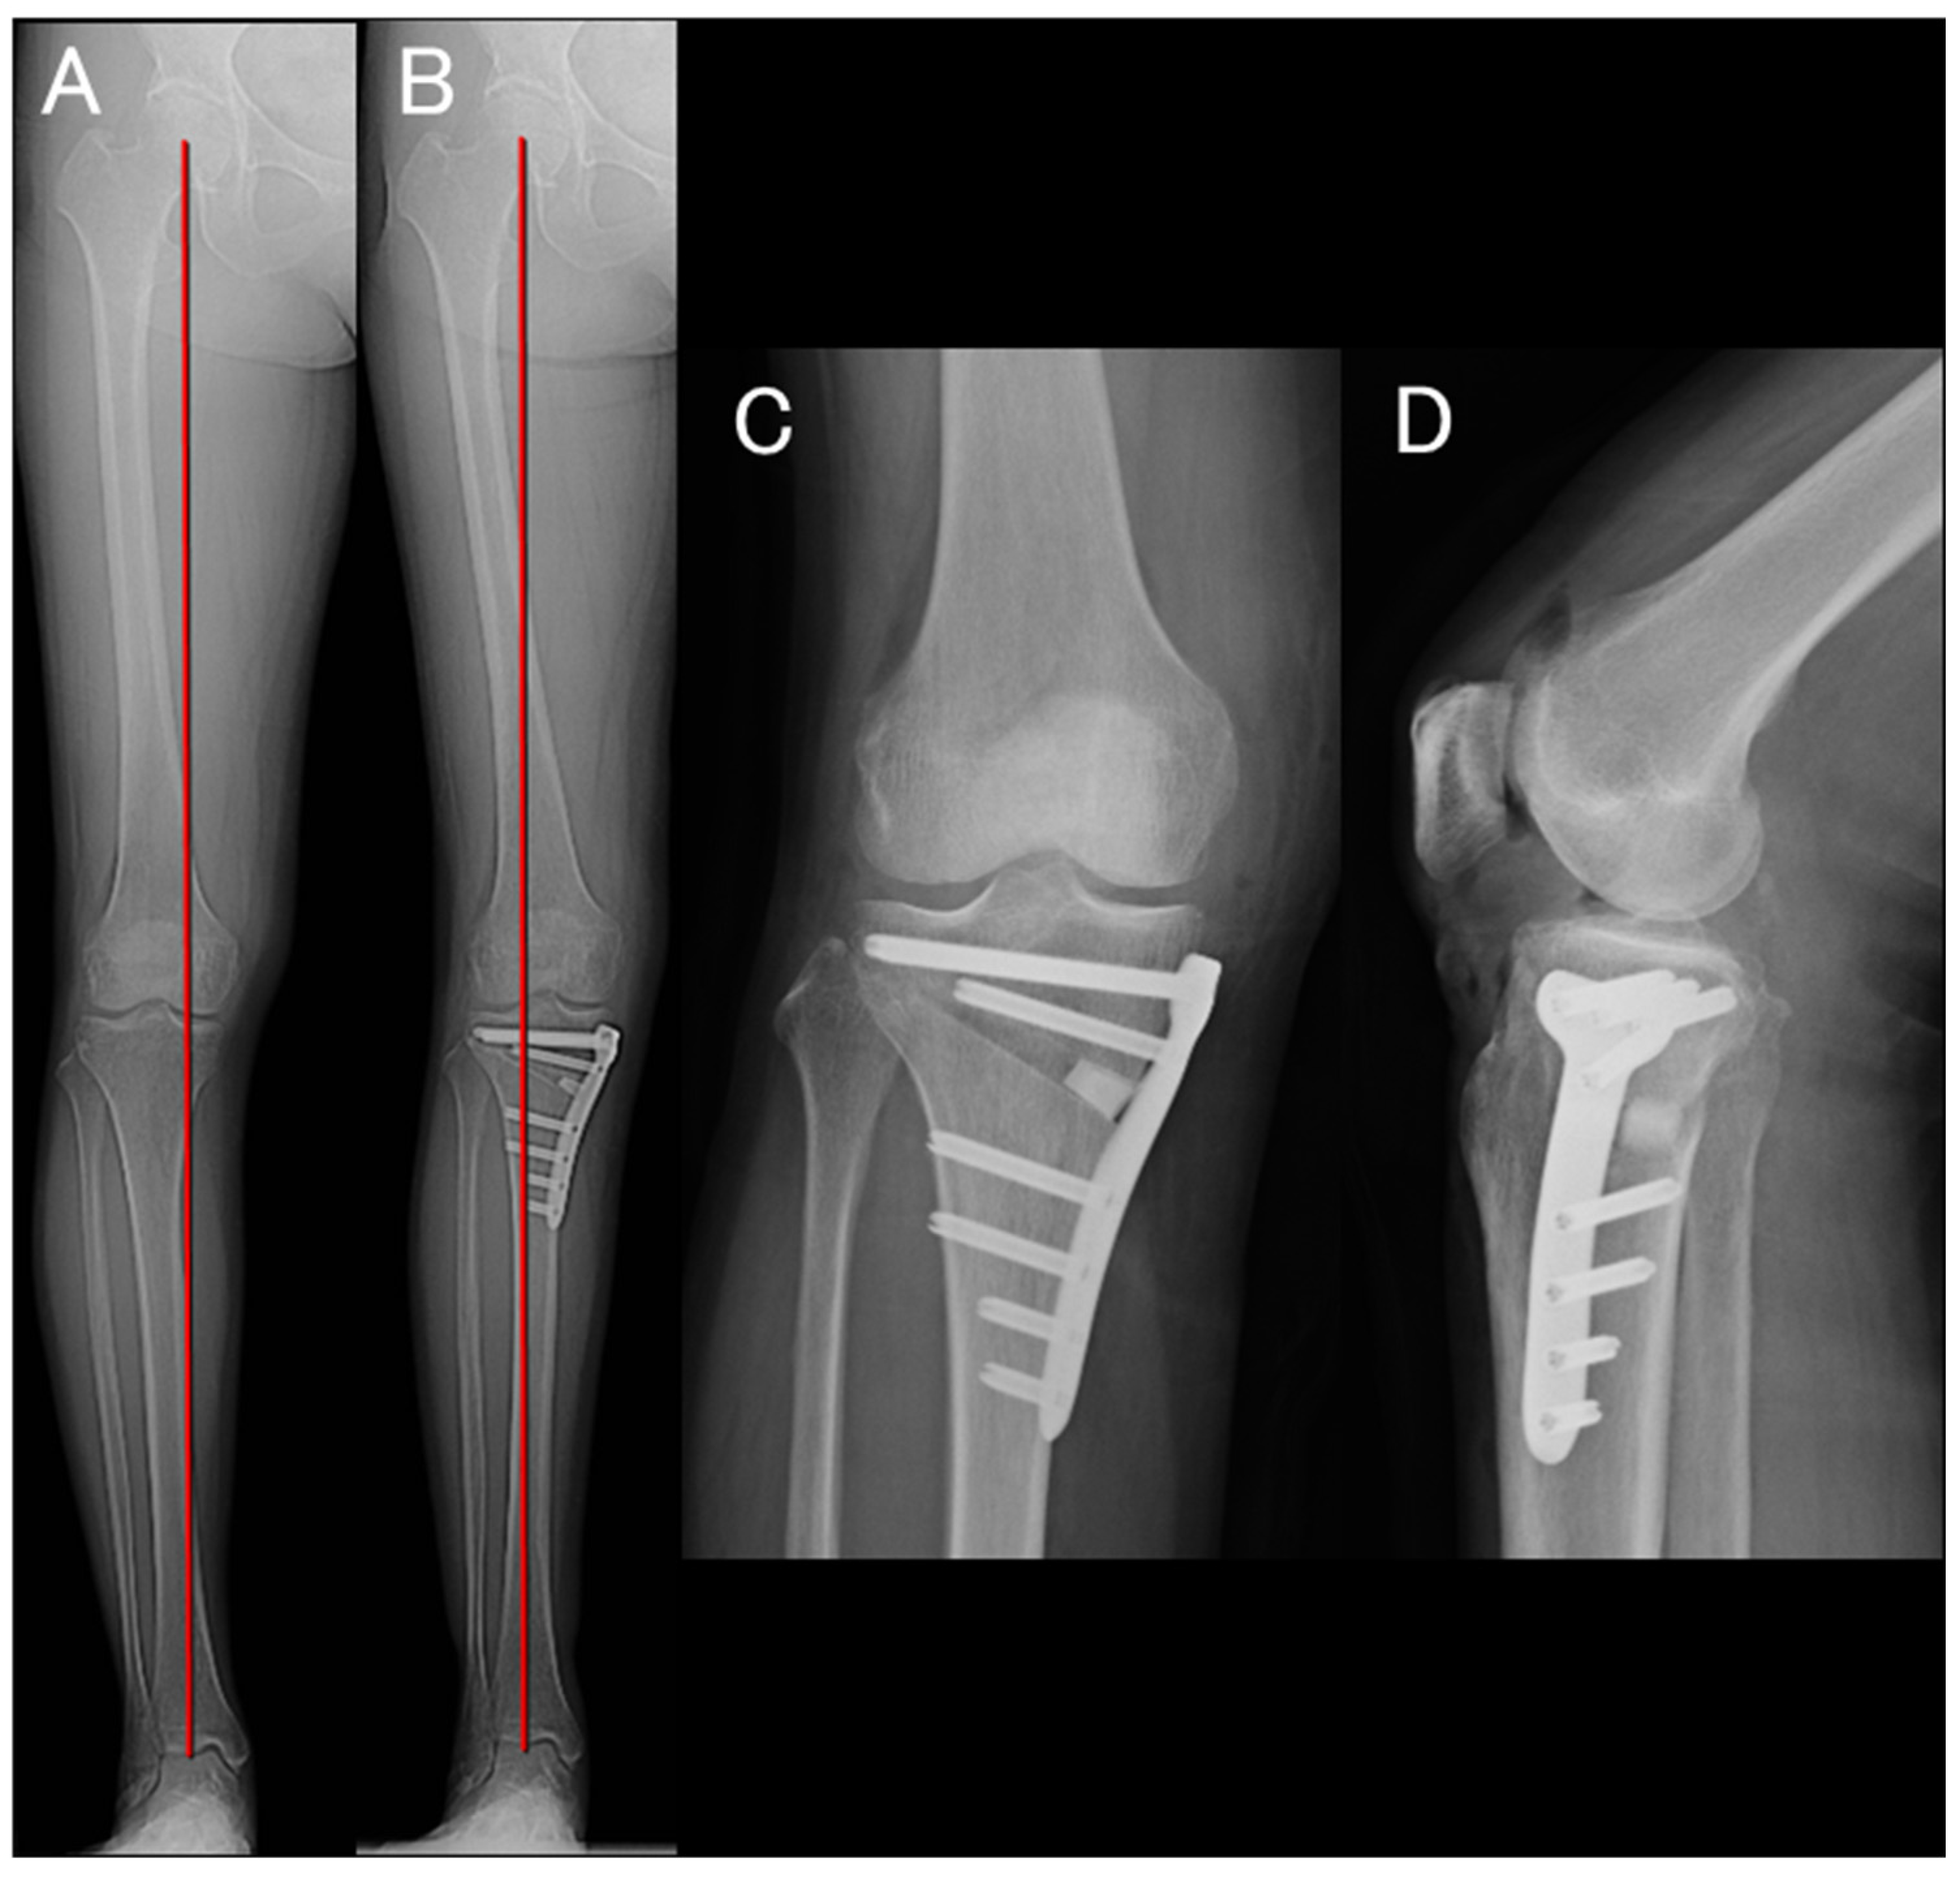

After completion of the arthroscopic procedure, OWHTO was performed in the same manner as in cases without meniscal repair [23,25]. Fixation was achieved using a TriS plate (OSferion Biomaterials, Tokyo, Japan), and the bone substitute was inserted into the osteotomy gap (OSferion 60 Marvelous, OSferion Biomaterials) (Figure 2). WBLR was adjusted to 58–72% of the tibial plateau width depending on the severity of osteoarthritis and cartilage condition [26,27].

Figure 2. (A) Preoperative standing full-length anteroposterior radiograph of the lower extremity showing WBLR of 28.4%. (B) Postoperative standing full-length anteroposterior radiograph of the lower extremity showing WBLR of 63.4%. (C) Postoperative anteroposterior radiograph showing an 8 mm medial opening gap. (D) Postoperative lateral radiograph demonstrating that the bone substitute was inserted to provide firm posterior–medial support.